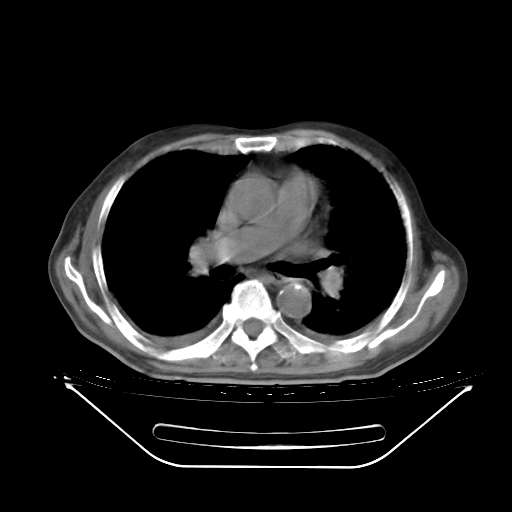

今天复查肺部CT,发现双肺广泛磨玻璃样改变。所以我把3月19日和5月9日相隔50天的肺部CT上传。请大家会诊。

2009年3月19日肺部CT片。

2009年3月19日肺部CT